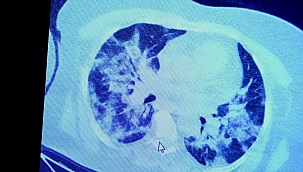

"Mutasyona uğrayan virüs ülkemize de girerse ciddi bir dalga ile karşı karşıya kalacağız"

Koronavirüs mutasyona uğradı